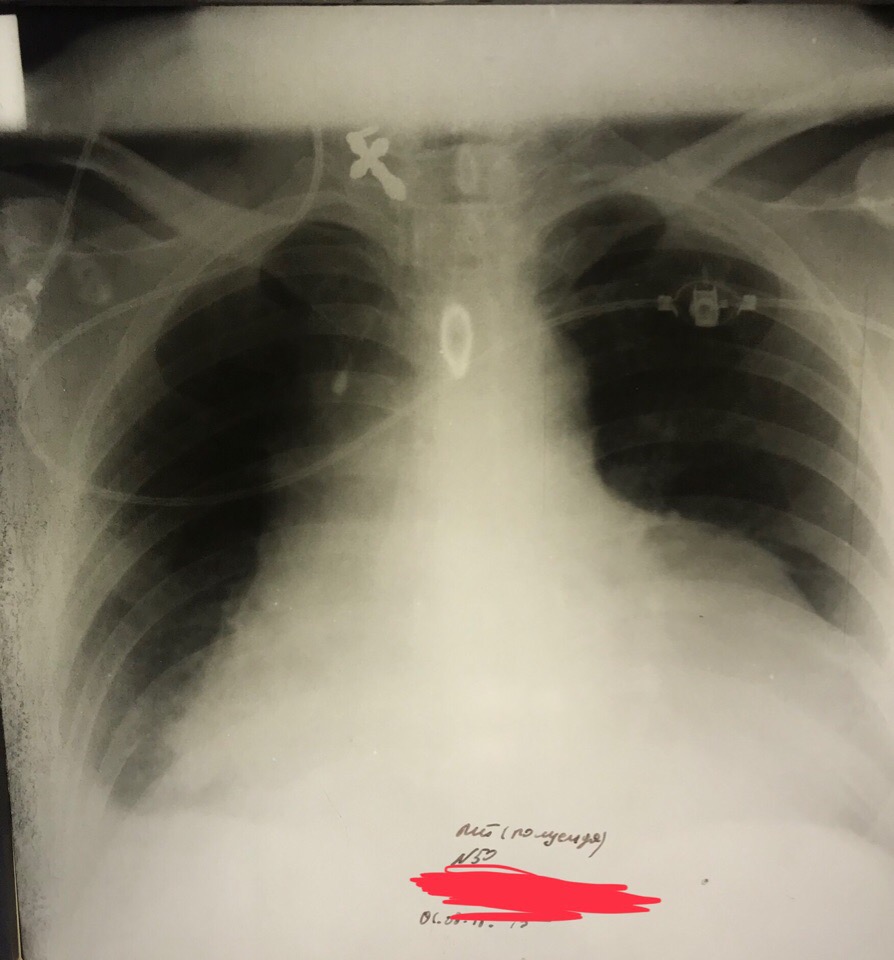

Заголовок сообщения: Эксудативный перикардит

Обсуждалось здесь https://vk.com/club84409679?w=wall-84409679_8904%2Fall

F5VlO9t1UOQ.jpg

F5VlO9t1UOQ.jpg [ 120.41 KiB | Просмотров: 12543 ]